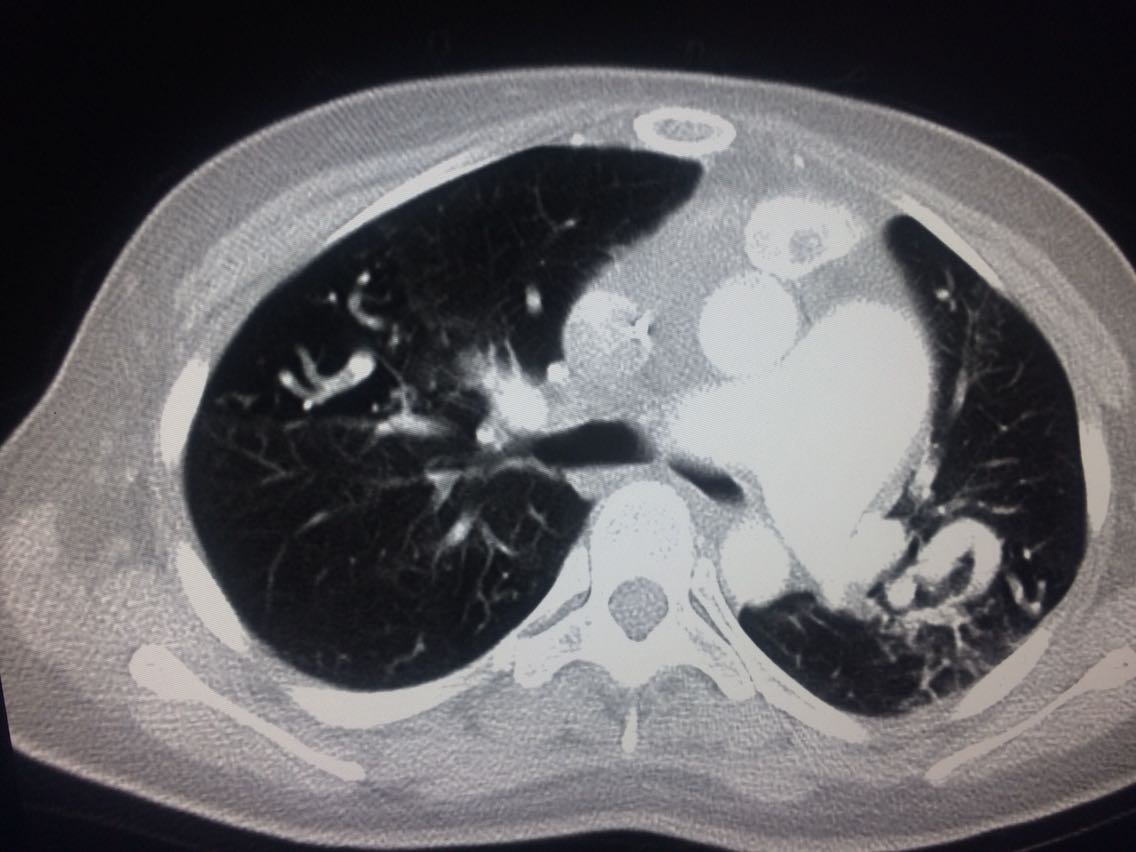

诊断,肺动脉高压。 鉴别诊断,肺动脉栓塞。 影像诊断,肺动脉高压,肺门区出现残根征,肺动脉扩张,肺动脉段膨隆,心影增大。CTA见迂曲增宽的肺动脉。 肺栓塞,影像可见典型充型缺损影,伴随肺纹理的减少。 治疗以对症处理为主,病人病史14年。 讨论诊断和鉴别诊断? 随访,症状好转。